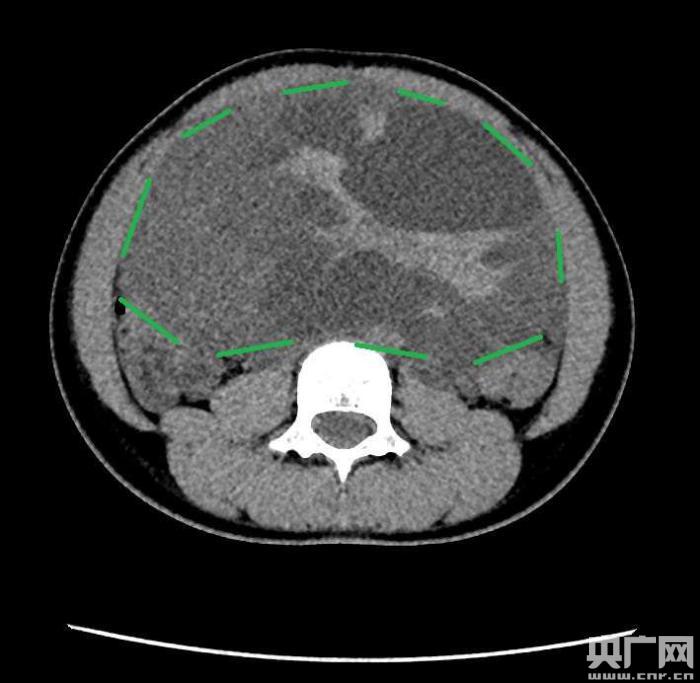

入院后,普外一科肖東主任向家長詢問了病史,仔細(xì)進(jìn)行了體格檢查,并完善腹部CT。CT結(jié)果提示,孩子的大部分腹腔、盆腔被一個(gè)巨大的腫瘤占據(jù),腸道、血管和腎盂都受到了不同程度的壓迫。從CT上看,腫瘤很可能起源于左側(cè)的卵巢。

肖東主任分析,孩子的腹腔腫瘤體積巨大,已經(jīng)出現(xiàn)了壓迫癥狀,且瘤體張力較高,隨時(shí)可能出現(xiàn)腫瘤自發(fā)性破裂出血,甚至危及生命,亟需手術(shù)治療。結(jié)合影像學(xué)檢查資料,醫(yī)生們制定了周密的手術(shù)方案。在向家長詳細(xì)告知了病情,并取得家長的知情同意后,5月2日下午,由肖東主任醫(yī)師主刀,任鋒副主任醫(yī)師及儲冬冬主治醫(yī)師協(xié)助,為小琪進(jìn)行了手術(shù)。

手術(shù)中發(fā)現(xiàn),小琪腹中的腫瘤體積巨大,大小約為25×20×15厘米,表面光滑,來源于左側(cè)卵巢。醫(yī)生們首先將其與周圍的組織小心剝離,然后將這個(gè)占據(jù)孩子腹腔、盆腔大部分的巨大包塊完整切除,切除腫瘤后還重建了左側(cè)卵巢。剖開瘤體,發(fā)現(xiàn)瘤體為囊性及實(shí)性混合組成,瘤體內(nèi)部充盈著粘液狀的液體,重量達(dá)到了3000克。術(shù)后小琪病情穩(wěn)定,測量腹圍從術(shù)前的72厘米減小到了62厘米。